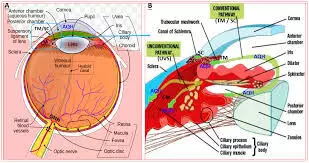

A study assessed the effect of an intensive initial IOP lowering treatment strategy on the progression of visual field damage. A total of 242 patients with newly detected early or moderate untreated open-angle glaucoma were enrolled at two university hospitals in Sweden. Participants were randomly allocated (1:1) to either initial treatment with intensive IOP-lowering medications followed by 360° laser trabeculoplasty (LTP), or to traditional mono-therapy, which was increased when deemed necessary. The primary study outcome of interest was the predicted remaining visual field, as measured by the visual field index (VFI) at projected end of life. Results: The median untreated IOP was 24 mmHg in both treatment groups. During follow-up, median and mode IOP was 17 mmHg in the mono- and 14 mmHg in the multi-treated group. In the mono-treated group the median VFI at projected end of life was 79.3%, and in the multi-treated group 87.1%, p=0.15. Annual rate of progression of visual field damage was faster in mono-treated than in multi-treated participants; median losses per year were 0.65 and 0.25 percentage units respectively, p=0.09. Progression events occurred in 21% of the mono- and in 11% of the multi-treated participants, p=0.03. Adverse events, mostly mild, were reported in 25% of the mono-, and in 36% of the multi-treated participants. Differences in visual field outcomes between treatment groups were more pronounced in participants having higher baseline IOP defined by median split of untreated IOP values. In the overall analysis the visual field outcomes were not overwhelming better in the multi-treated group, but post-hoc analysis showed definite benefit in patients with higher untreated IOP. Based upon the results of this study, initial intensive treatment may be considered in glaucoma patients with high untreated IOP at diagnosis, while we found no evidence that multi-therapy should be given routinely to all glaucoma patients.